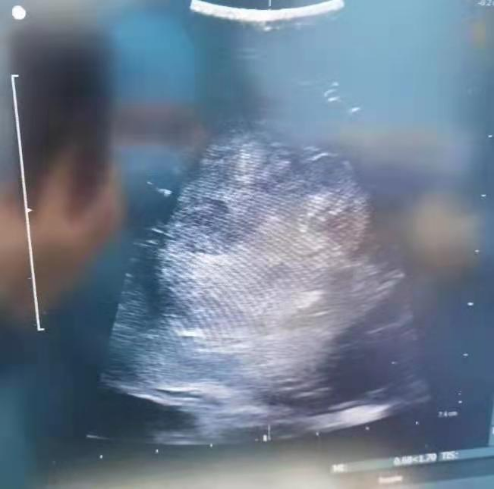

术中超声可见肿瘤异常回声

为什么要多超声这一辅助装置?术中超声容易显示血供丰富的病变,低级别胶质瘤可通过增强色阶显示肿瘤范围。不同病理特点,不同深度的胶质瘤其超声声像图表现有所差异。B型超声在切除脑胶质瘤术中能够准确判定肿瘤的位置,为术者选择何种手术入路、何处切开皮层等方面提供了明确且价值重要的依据。并可以实时监测胶质瘤的切除,减少残留程度,使肿瘤切除的精确度及患者功能保护得到了极大提高,尤其是切除功能区和深部胶质瘤重要的辅助手段。